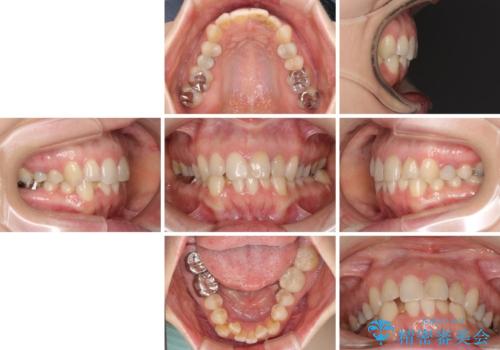

- 前歯のデコボコと奥歯の虫歯を気にして来院された患者様です。

主に下顎歯列全体の後方移動とIPR(歯と歯の間を削る)によってデコボコが解消するように設計し、インビザラインにより治療を行うこととしました。

矯正治療後半に下顎左右奥歯をセラミッククラウンにて補綴し、その後インビザラインによる歯列の仕上げを行うこととしました。

下顎前歯の叢生が速やかに改善されたため、1年3か月で治療を終えることができました。

下顎前歯は後戻りを起こしやすいため、舌側を細いワイヤーで固定することで後戻り対策を行っています。